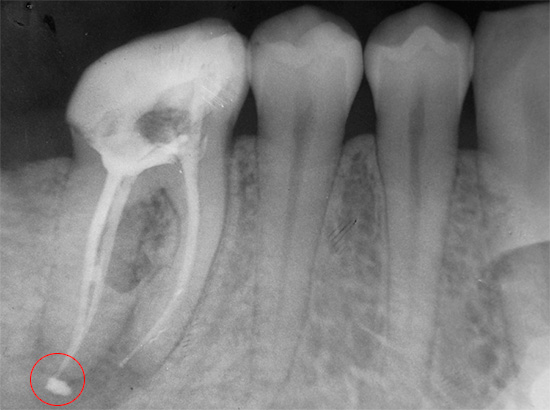

- Riempimento del canale con la rimozione di materiale oltre la radice. Questo errore porta a un dolore di lunga durata quando si preme sul dente, nonostante un riempimento correttamente installato.

- Riempimento del canale non fino all'apice (apice). Il canale dovrebbe normalmente essere sigillato per l'intera lunghezza di lavoro. Se ciò non accade, a un certo punto è vuoto. La natura non tollera il vuoto, quindi, i microbi si accumulano nell'area non sigillata, che successivamente provocano infiammazione alla radice. Alcune persone immediatamente o dopo qualche tempo hanno dolori doloranti sotto il riempimento, o un dente sigillato fa male quando viene premuto su di esso. In questo caso, è necessario ritrattare e riempire nuovamente il canale.

- Strumento rotto nel canale. In questo caso, la complicazione sorge a causa del lasciare un pezzo di uno strumento dentale nel canale con una fonte di infezione - un "nervo" infiammato o con batteri non lavati fuori dal canale. In futuro, questo spesso porta a dolore dopo aver riempito i canali dentali - immediatamente o dopo alcune settimane (a volte anni).